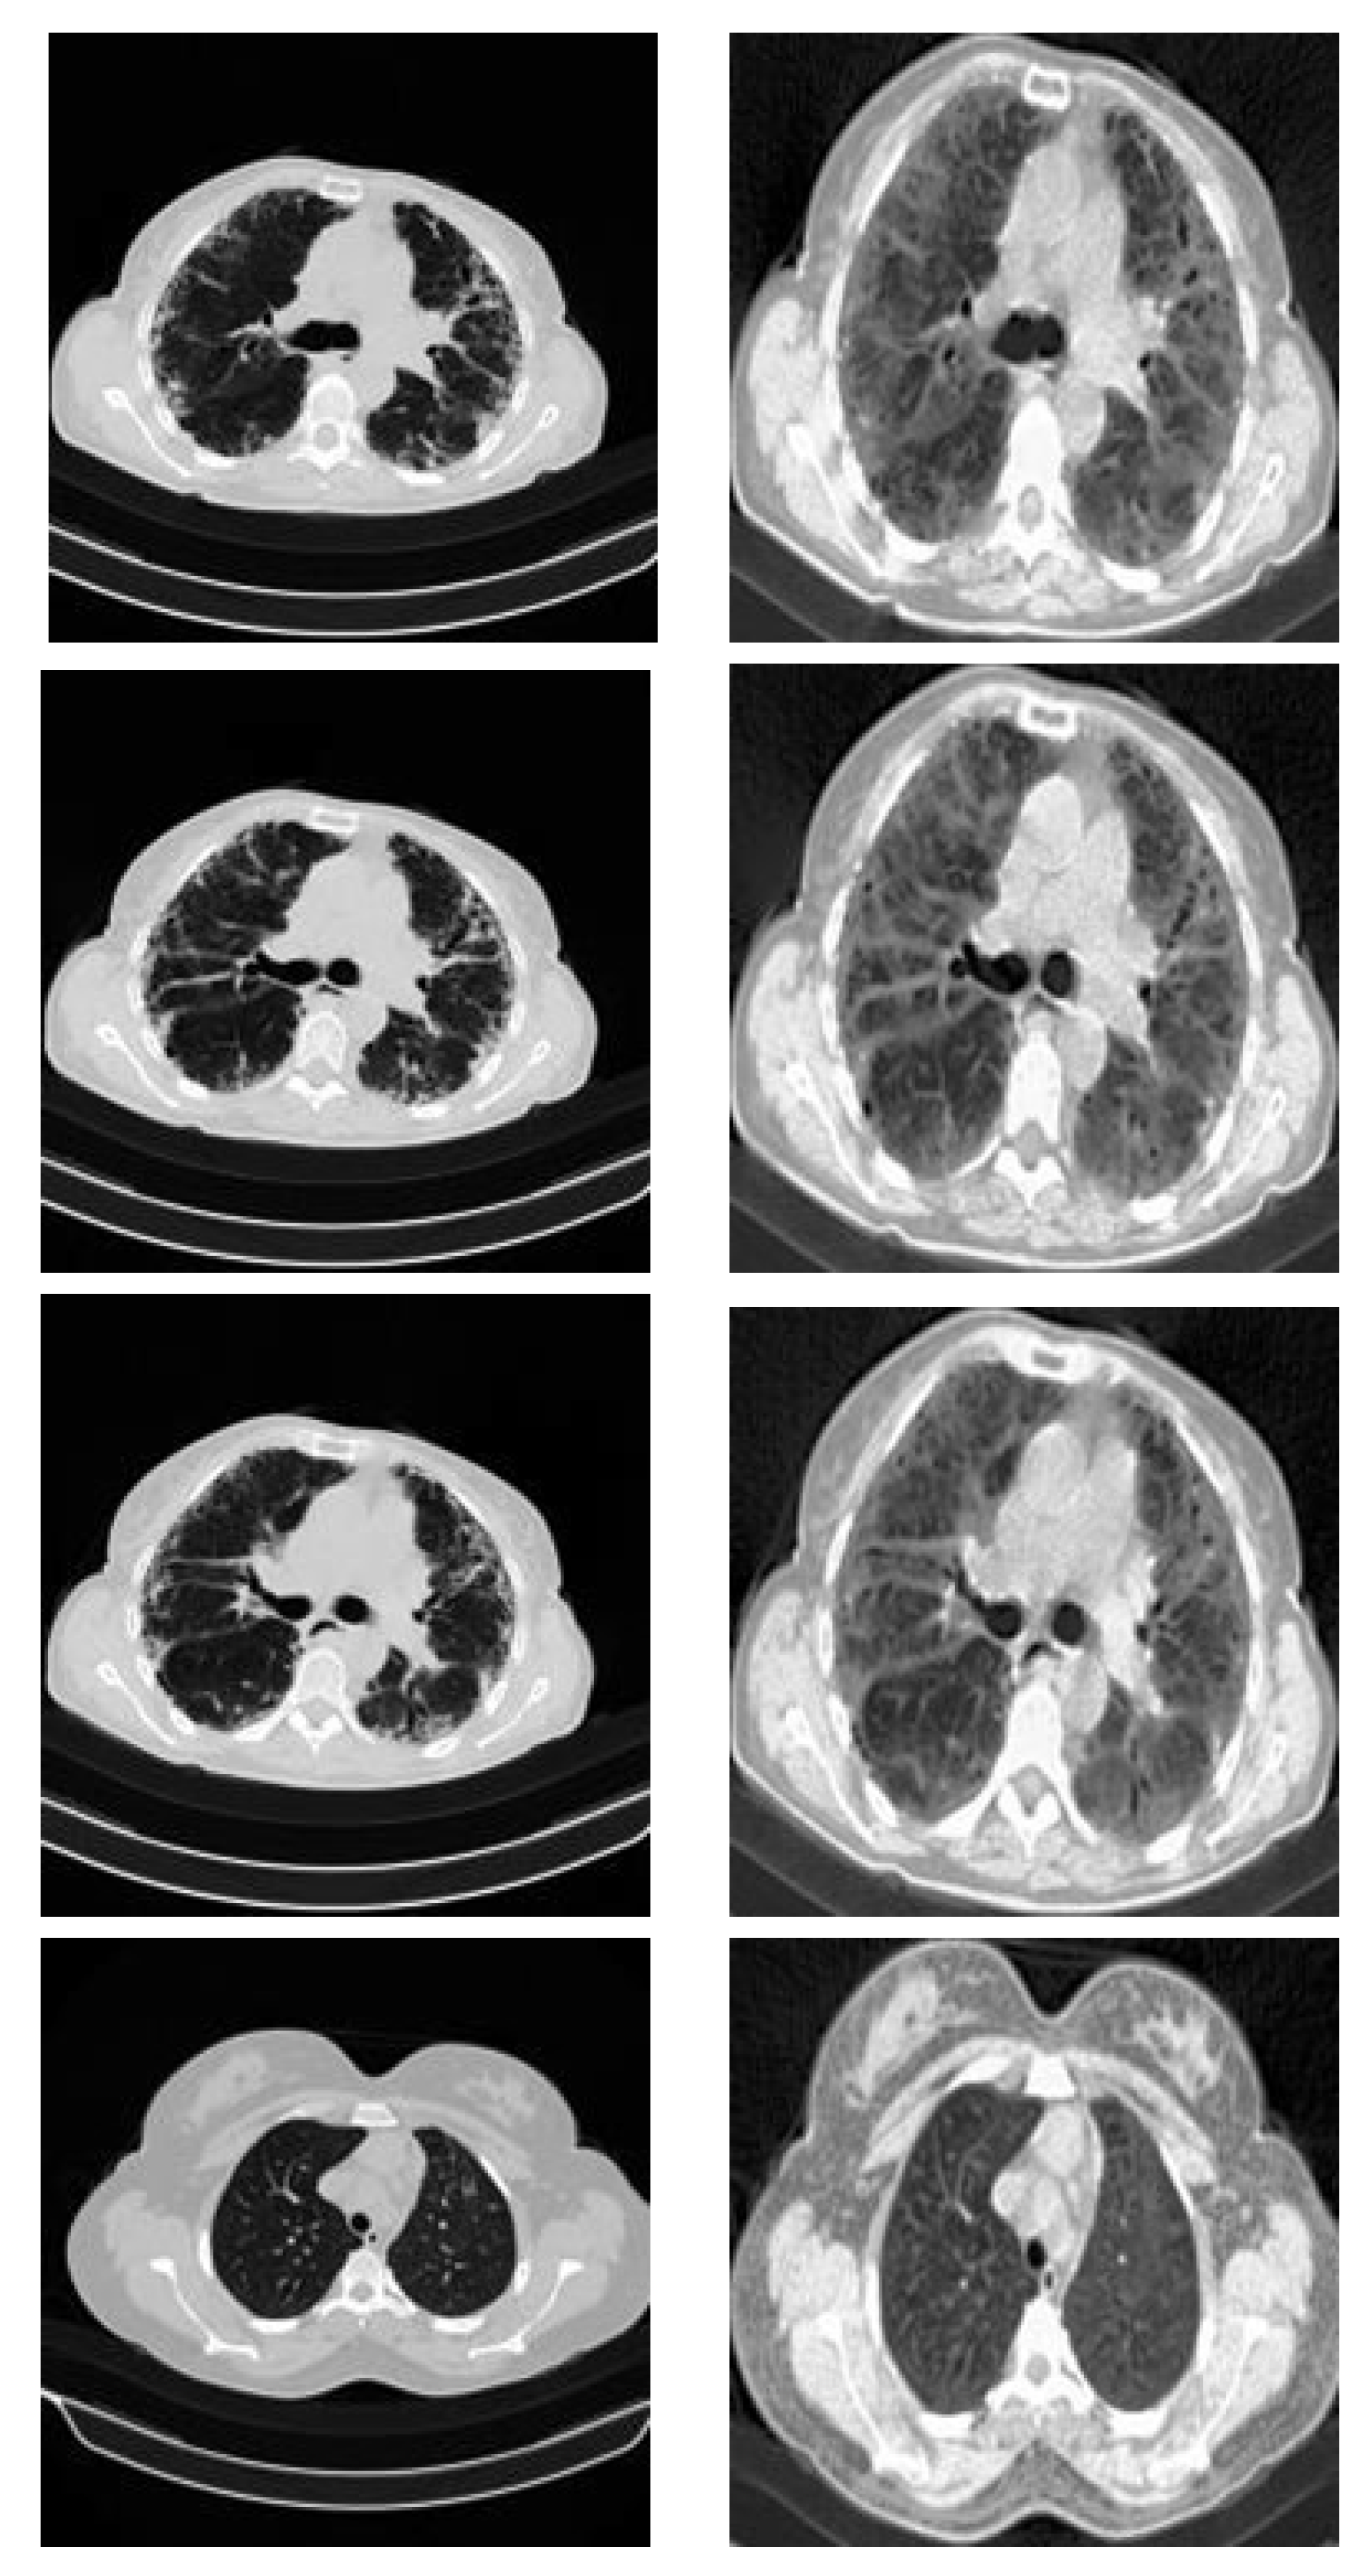

3.3.2. CT Scan Dataset

- Morozov, S.P.; Andreychenko, A.; Pavlov, N.; Vladzymyrskyy, A.; Ledikhova, N.; Gombolevskiy, V.; Blokhin, I.A.; Gelezhe, P.; Gonchar, A.; Chernina, V.Y. Mosmeddata: Chest ct scans with covid-19 related findings dataset. arXiv 2020, arXiv:2005.06465. [Google Scholar]